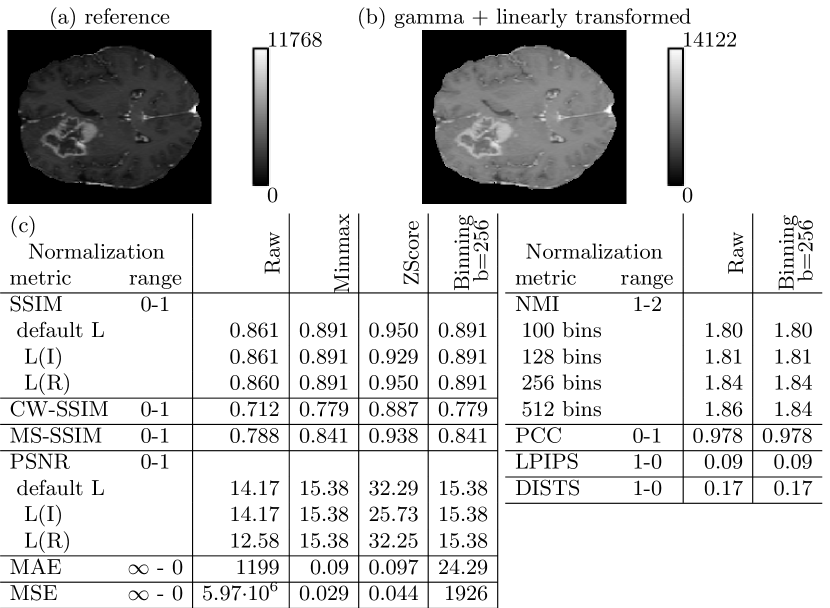

3.1 Pitfall 1: Inappropriate Normalization

Challenges with normalization arise, when the intensity value ranges of two images and are not equal. When shape of the histograms of and are not alike, metric evaluation after Zscore normalization may deviate from evaluation after Minmax normalization. Also, small deviations of the data range parameter for SSIM and PSNR may have a noticeable effect on the metric scores.

We distorted the images by applying a gamma transform with and subsequent linear scaling with and calculate the metrics in comparison to the undistorted original images. We evaluated SSIM and PSNR with the default data range (see Sec. 2.2), but also with and . We evaluated all metrics with Minmax, Zscore and without normalization as well as with binning to 256 bins (see Eq. 2). As LPIPS and DISTS require images with an intensity range fixed to and respectively, default application includes a normalization according to Eq. 1 with and and Minmax normalization respectively. Therefore, the learned metrics are not additionally evaluated with Minmax and Zscore normalization. PCC and NMI are, by definition (see Sec. 2.2), not sensitive to normalization as defined in Eq. (1) and are also not evaluated with Minmax and Zscore normalization. However, we evaluate NMI for internal binning with 128, 256 and 512 bins.

The results in Fig. 1 show that SSIM and PSNR increase for higher data ranges and decrease for binned data. Zscore and Minmax normalization result in noticeably different metric scores, because reference and transformed images have different intensity ranges and different means. NMI almost ignores the gamma and linear transform, when internally a high bin number is used and binning was not performed as pre-normalization. Smaller bin numbers and non-matching internal and pre-binning bin numbers may further reduce similarity artificially.